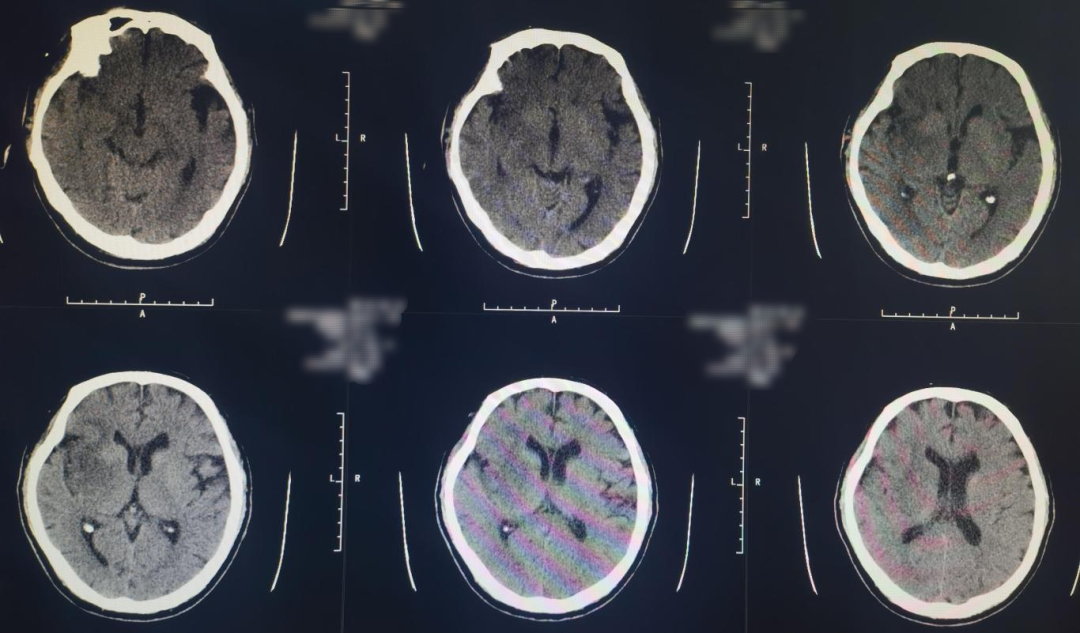

Cranial CT revealed a hyperdense sign in the right middle cerebral artery.

Immediate postoperative CT showed no secondary hemorrhage but mild contrast retention.

10-day postoperative follow-up cranial CT showed infarction in the right cerebral hemisphere.